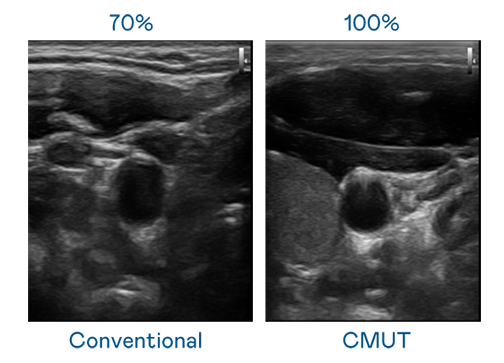

CMUT 技術是一種用電容式微機電元件來產生超音波訊號的技術。與傳統 PZT 壓電式技術相比,CMUT 頻寬增加 30%,更寬頻的超音波訊號讓影像解析度大幅提升,是實現高影像品質醫療超音波掃描、促進精準醫療發展的關鍵技術。

超音波影像的解析度高低,首先取決於探頭能發出的訊號頻寬。304永利集团 CMUT 可提供高清晰的超音波訊號,提供高頻寬、高靈敏度、影像紋理細節更高的超音波影像,協助醫護人員縮短影像判讀時間及利用精準的醫療影像進行診斷。